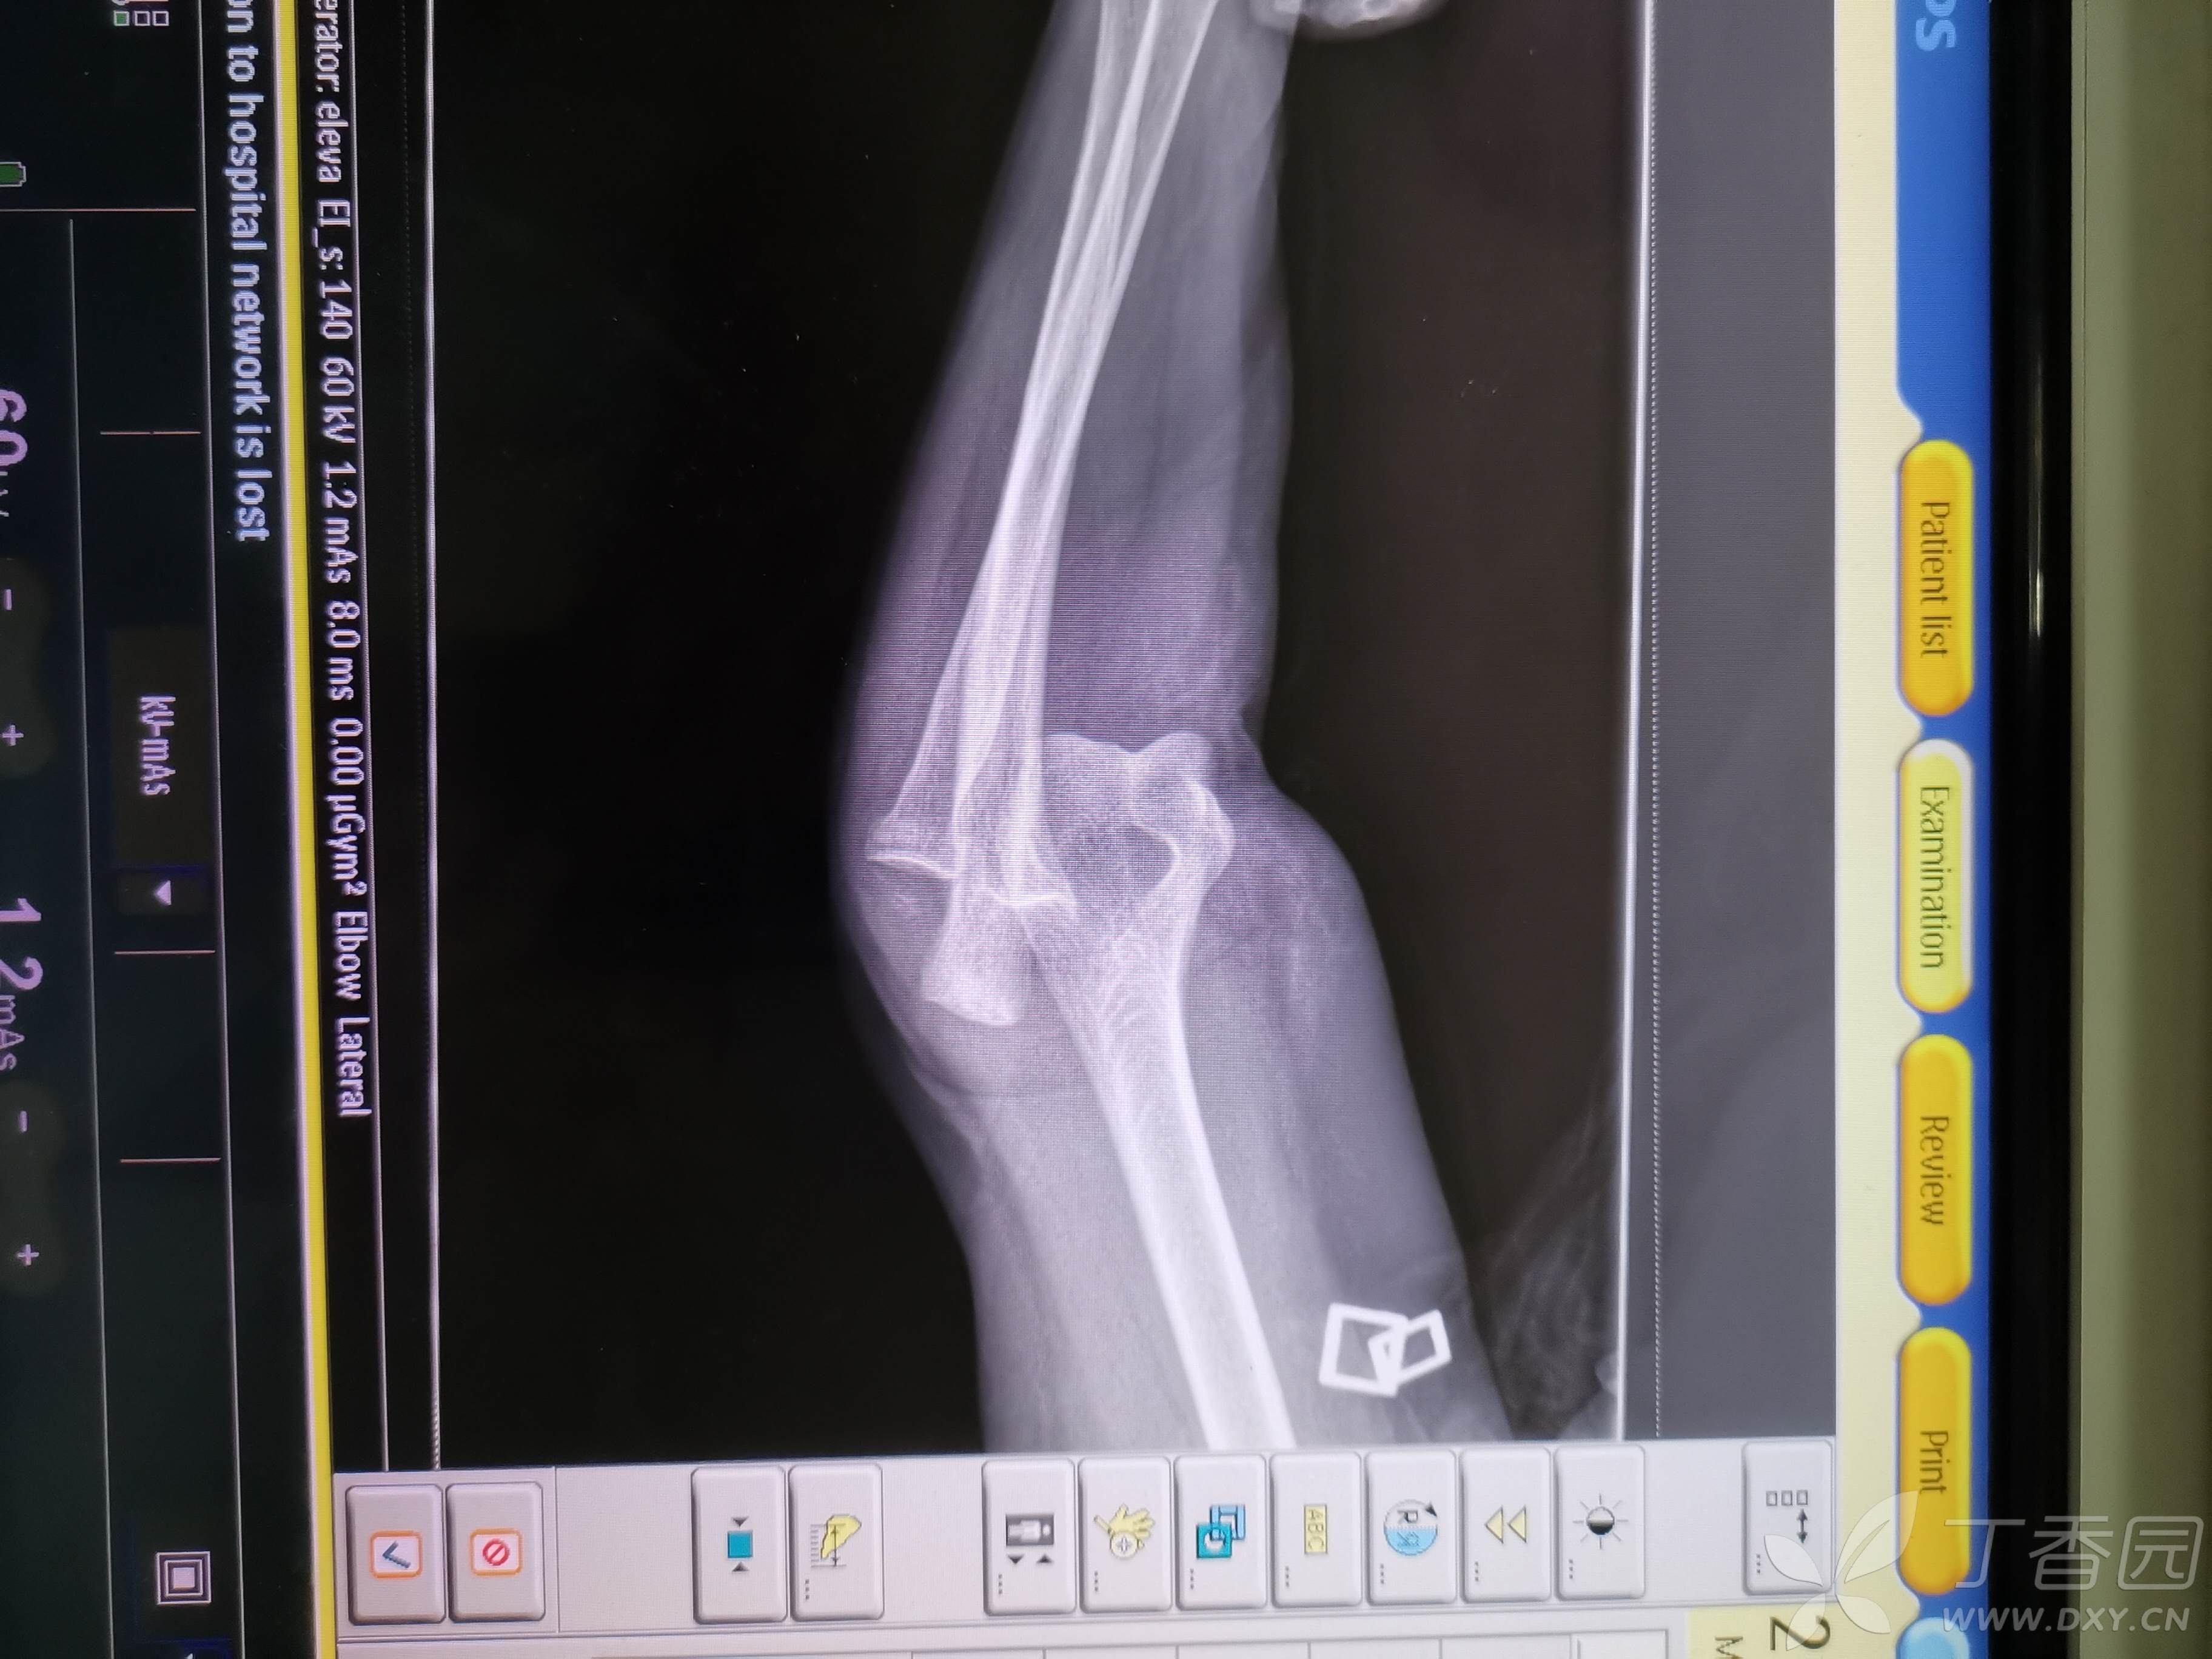

肘关节后脱位如何固定?

患者女,73岁,摔伤2小时入院

以上为脱位当时